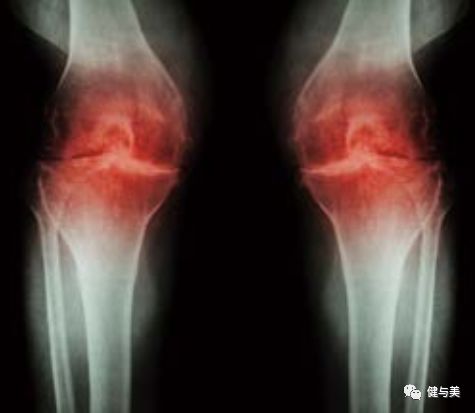

骨关节炎

就像神经过度兴奋会造成腿部抽筋一样,其他原因所导致的神经功能障碍也会造成抽筋。骨关节炎(关节炎中最常见的类型)通常表现为关节僵硬和疼痛。然而,骨关节炎患者也会经历肌肉痉挛和腿部抽筋。这种腿部抽筋通常与脊柱骨关节炎有关,严重时会导致神经痛或其他神经损伤。